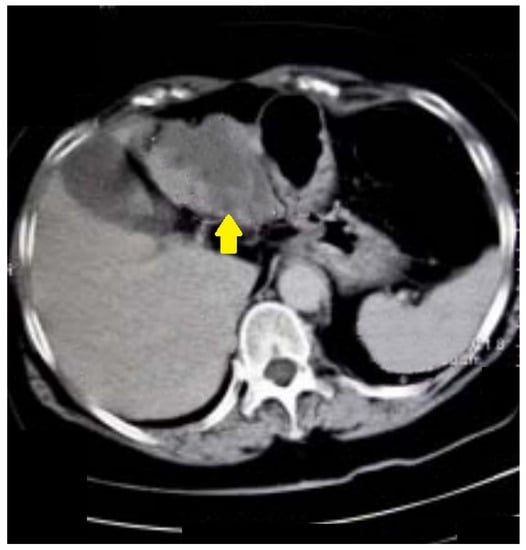

The same patient in the prone position allowed us to visualize carcinoma of the sigmoid colon that rose to the lumen (Figure 4). The differential diagnosis of the finding was residual intestinal contents, which required a change of the patient’s position. Placing the patient in a prone position did not show dynamics in the topic and characteristics of the lesion, which confirmed it was a tumor.

Figure 4.

CT colonography-axial scans in a prone position. The same 73-year-old patient with incomplete FCS due to intraluminal obturation of the sigmoid colon from carcinoma is presented in the figure showing a tumor with soft tissue density.